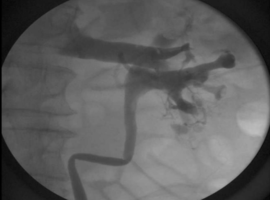

An Exceptionally Rare Retrograde Pyelogram Finding with an Unexpected Cause

DeSanto M*, Weber T, Hale N. (USA)